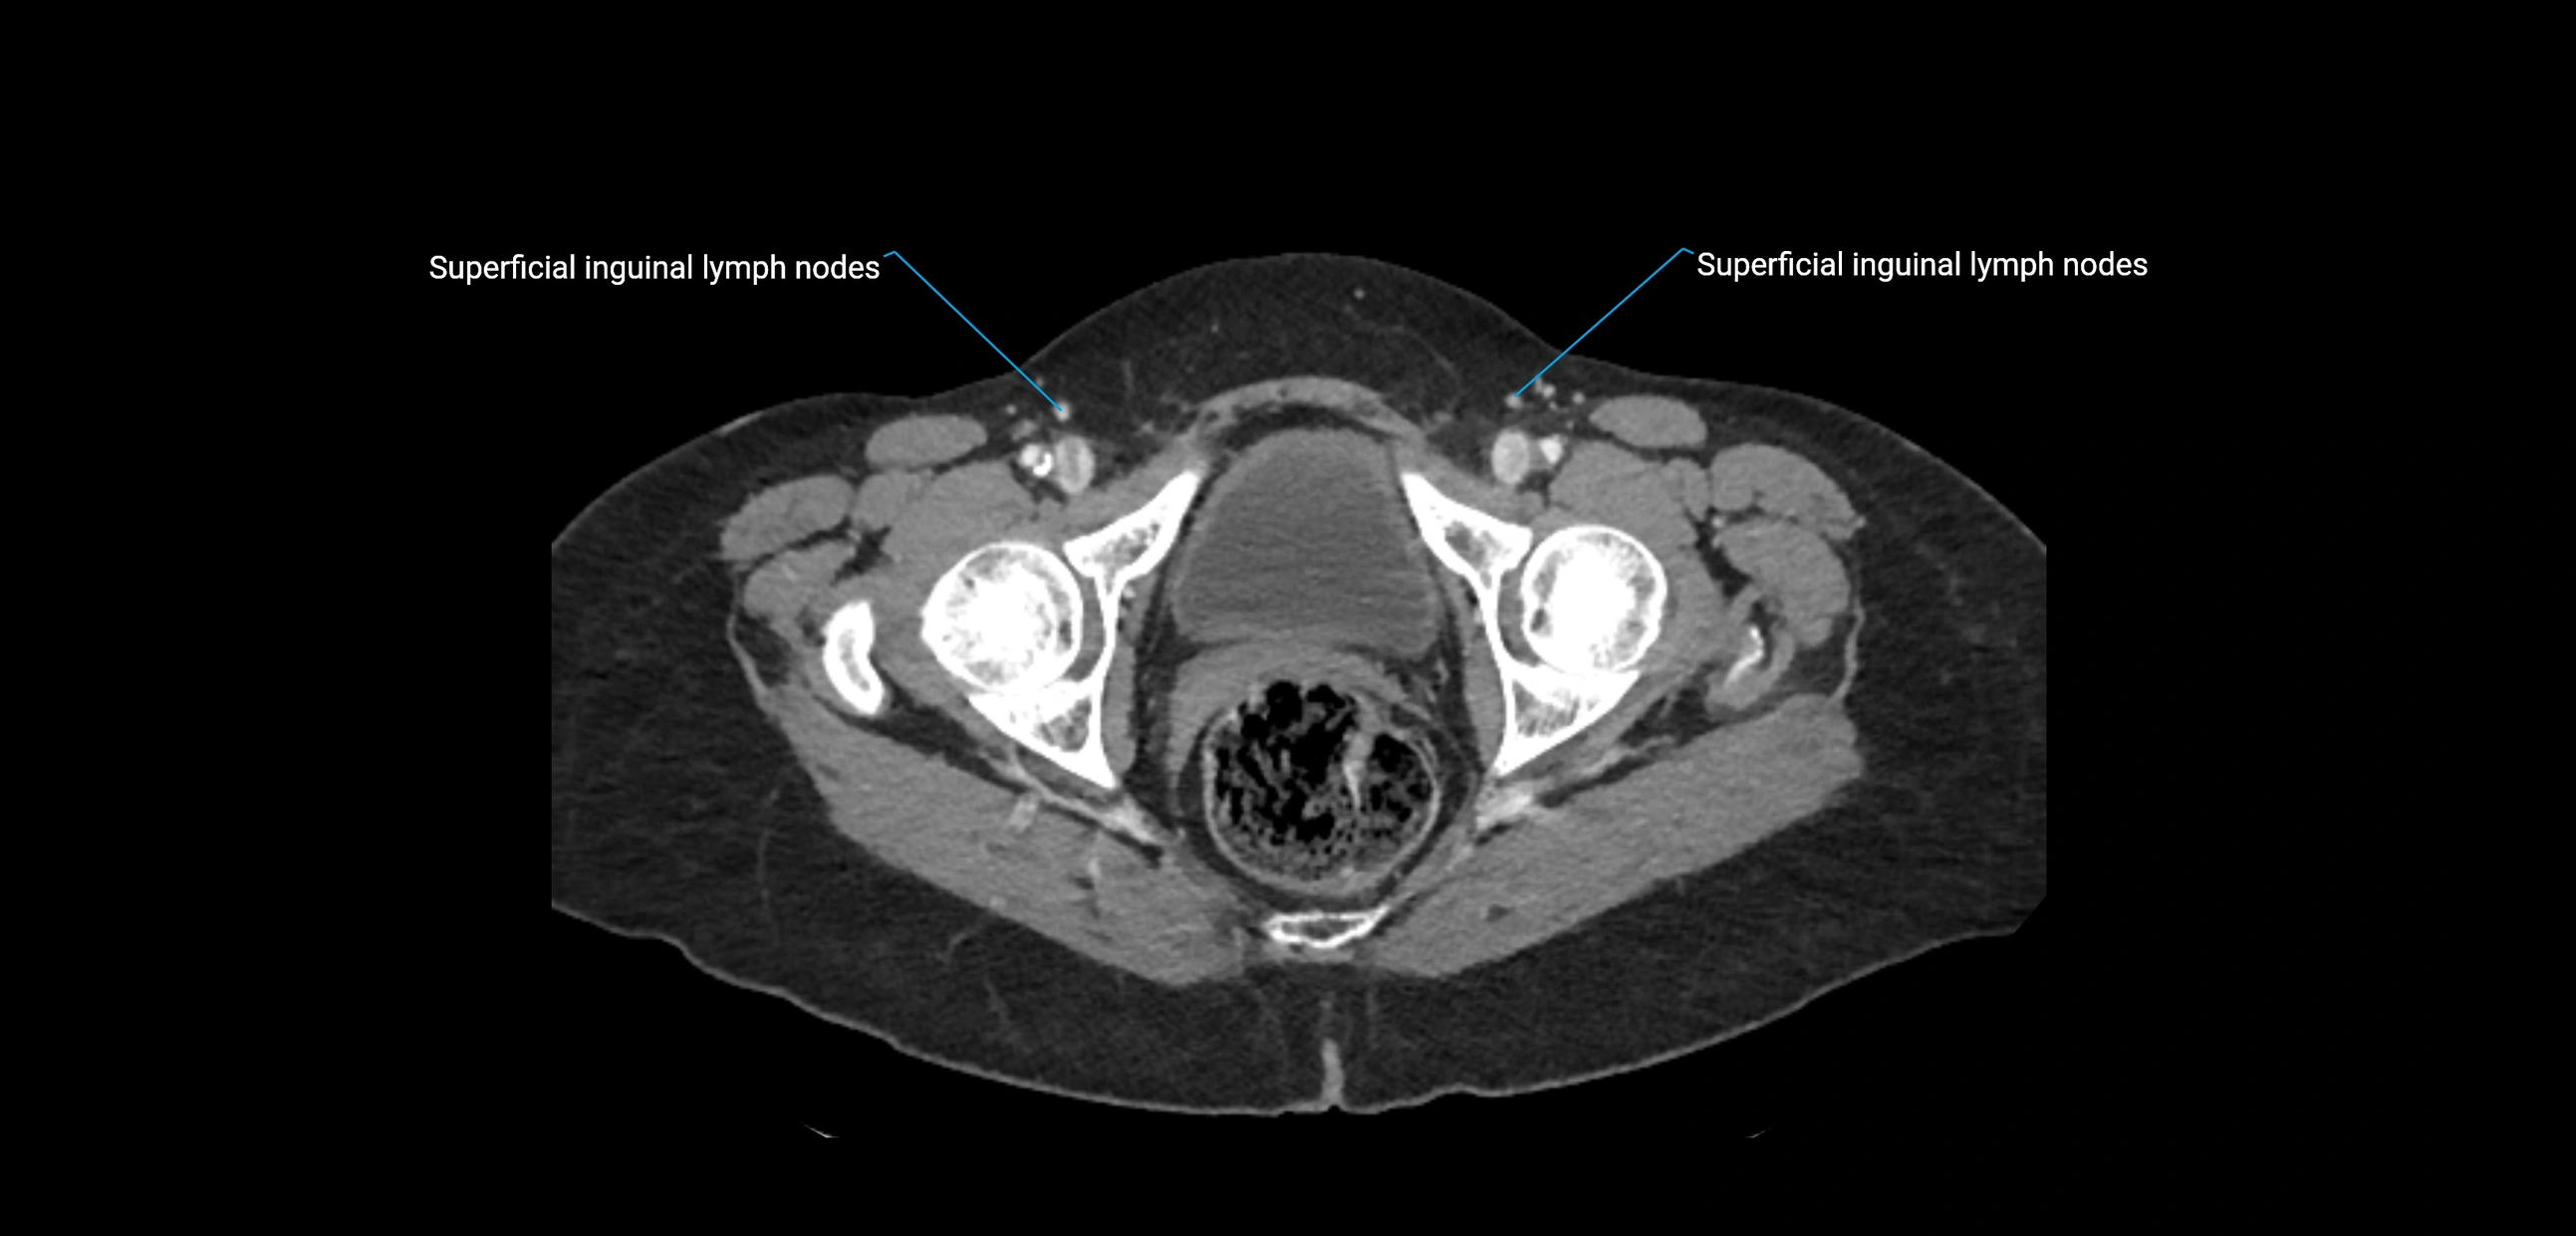

CT Appearance

CT Pre-Contrast:

• Nodes appear as soft-tissue density nodules adjacent to the aorta and IVC

• Calcification may be seen in chronic infections (e.g., tuberculosis)

CT Post-Contrast:

• Normal nodes enhance homogeneously

• Malignant nodes may show heterogeneous enhancement, central necrosis, or conglomerate formation

• Size >1 cm short axis is suspicious, though morphology and distribution are equally important